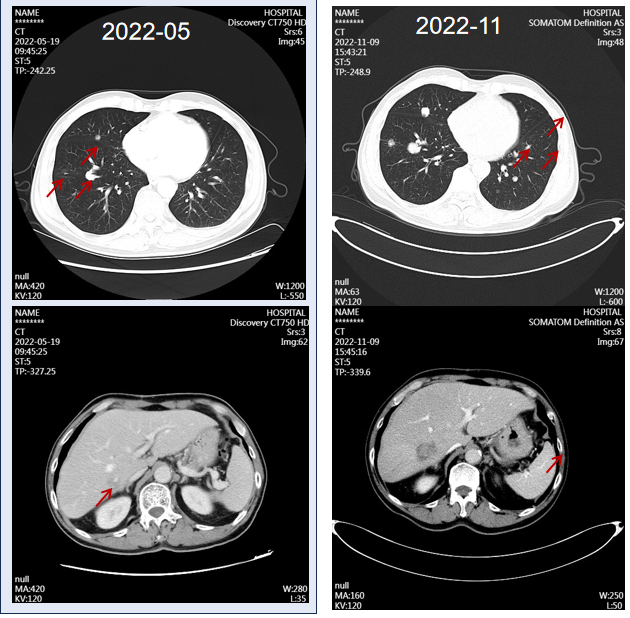

2022年11月复查胸腹部CT,提示(对比2022年5月)提示双肺结节增多、增大,肝右后叶占位增大(图4)。